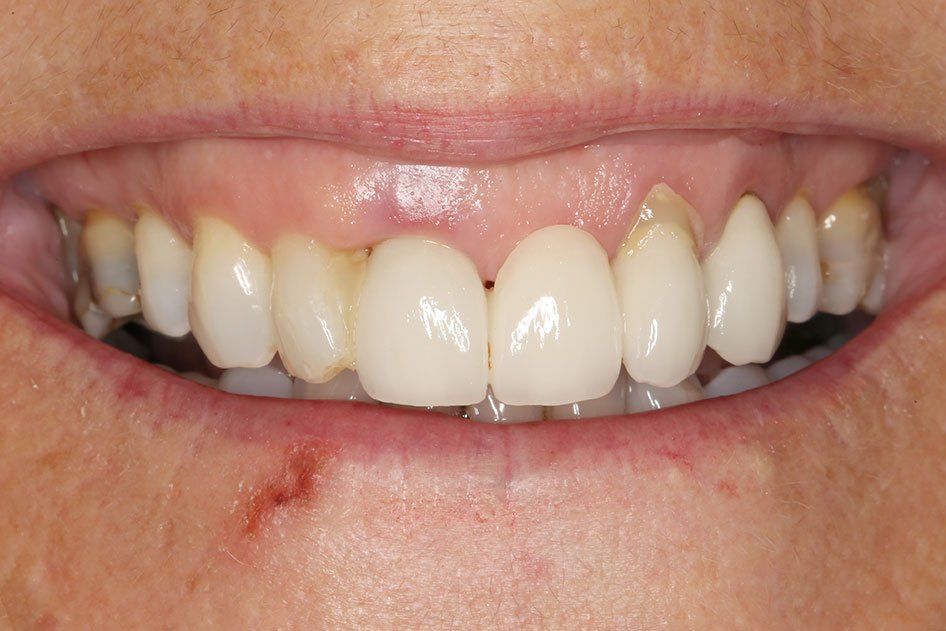

The implant crown is supported by the implant fixture. It is carefully crafted to look and feel like a healthy, natural tooth.

This provides the same stability as natural teeth, making it possible for your replacement teeth to look, feel and function like natural teeth.

Dental implants have a number of advantages over more conventional methods of replacing missing teeth. An implant-supported crown is very similar to your natural tooth because it is fixed permanently, and does not need your other teeth or soft tissues for support.